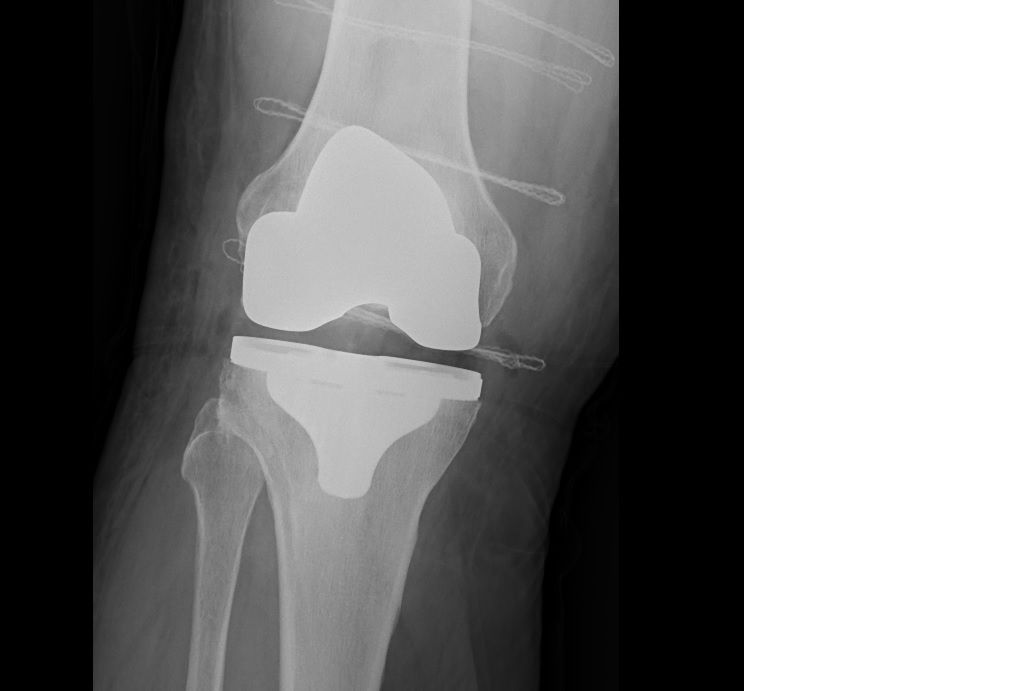

Choroba zwyrodnieniowe bioder i kolan - endoprotezoplastyki.

Zdjęcia i filmy